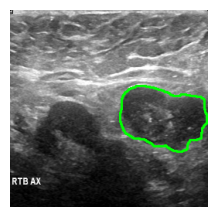

dataset = load_dataset("nielsr/breast-cancer", split="train")idx = 10

image = dataset[idx]["image"]

label = dataset[idx]["label"]

msk = np.array(label)

an_img = overlay_mask_border_on_image_frm_img(

image, msk,

)

show_(an_img)